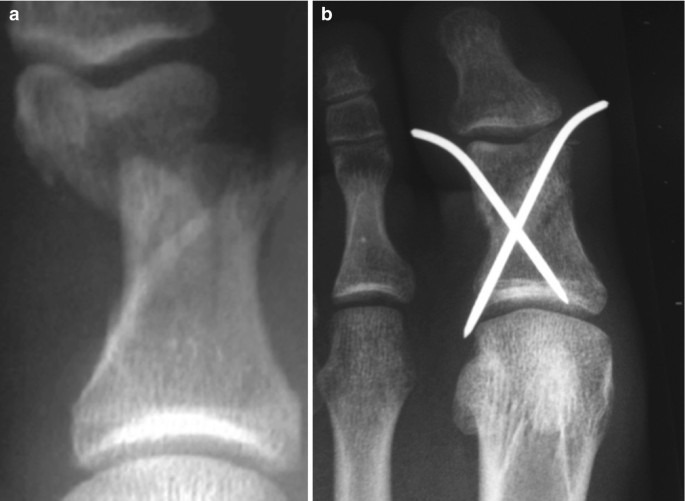

발가락 골절 수술

복합 골절이나 압박 골절의 경우 수술이 필요할 수 있습니다. 발가락 골절 수술 후 추가로 2-4주의 회복 기간이 필요하며, 비용은 60-150만원 정도로 다양합니다. 수술 방법에는 핀을 박는 방법과 금속판을 사용하는 방법이 있습니다.